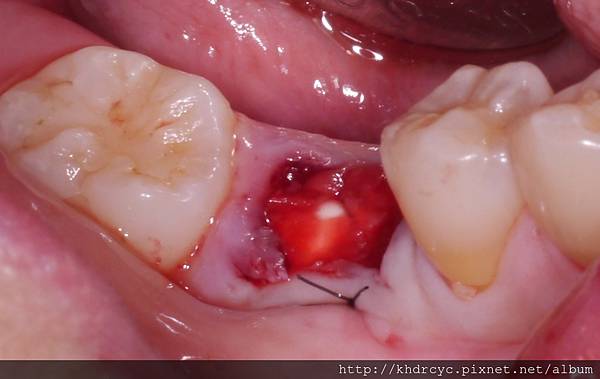

較明顯的是在傷口處沒有血塊生成

這就是典型的乾性齒槽炎

處理方法是用生理食鹽水沖洗

放置Eugenol敷料局部只痛

視情況3-6天內每天換藥即可